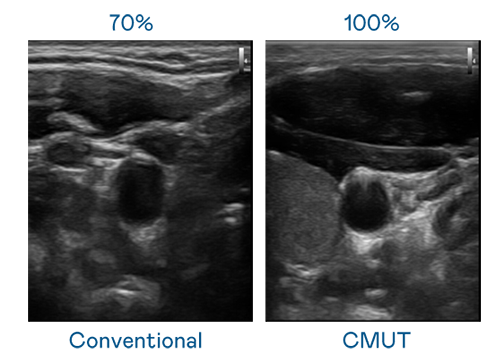

CMUT 技術是一種用電容式微機電元件來產生超音波訊號的技術。與傳統 PZT 壓電式技術相比,CMUT 頻寬增加 30%,更寬頻的超音波訊號讓影像解析度大幅提升,是實現高影像品質醫療超音波掃描、促進精準醫療發展的關鍵技術。

大頻寬帶來超清晰影像

超音波影像的解析度高低,首先取決於探頭能發出的訊號頻寬。羞羞视频18 CMUT 可提供高清晰的超音波訊號,提供高頻寬、高靈敏度、影像紋理細節更高的超音波影像,協助醫護人員縮短影像判讀時間及利用精準的醫療影像進行診斷。